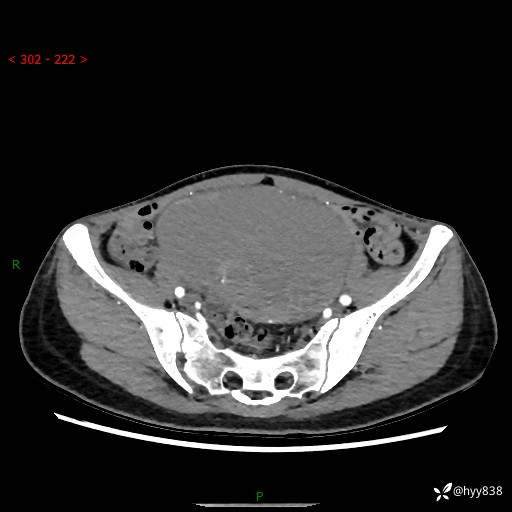

【患者信息】:女,50岁

【主诉】:外院超声发现腹盆肿块,为进一步诊治来我院,门诊已“盆腔肿块”收入院。

腹盆CT平扫+增强

【临床诊断】:盆腔肿瘤